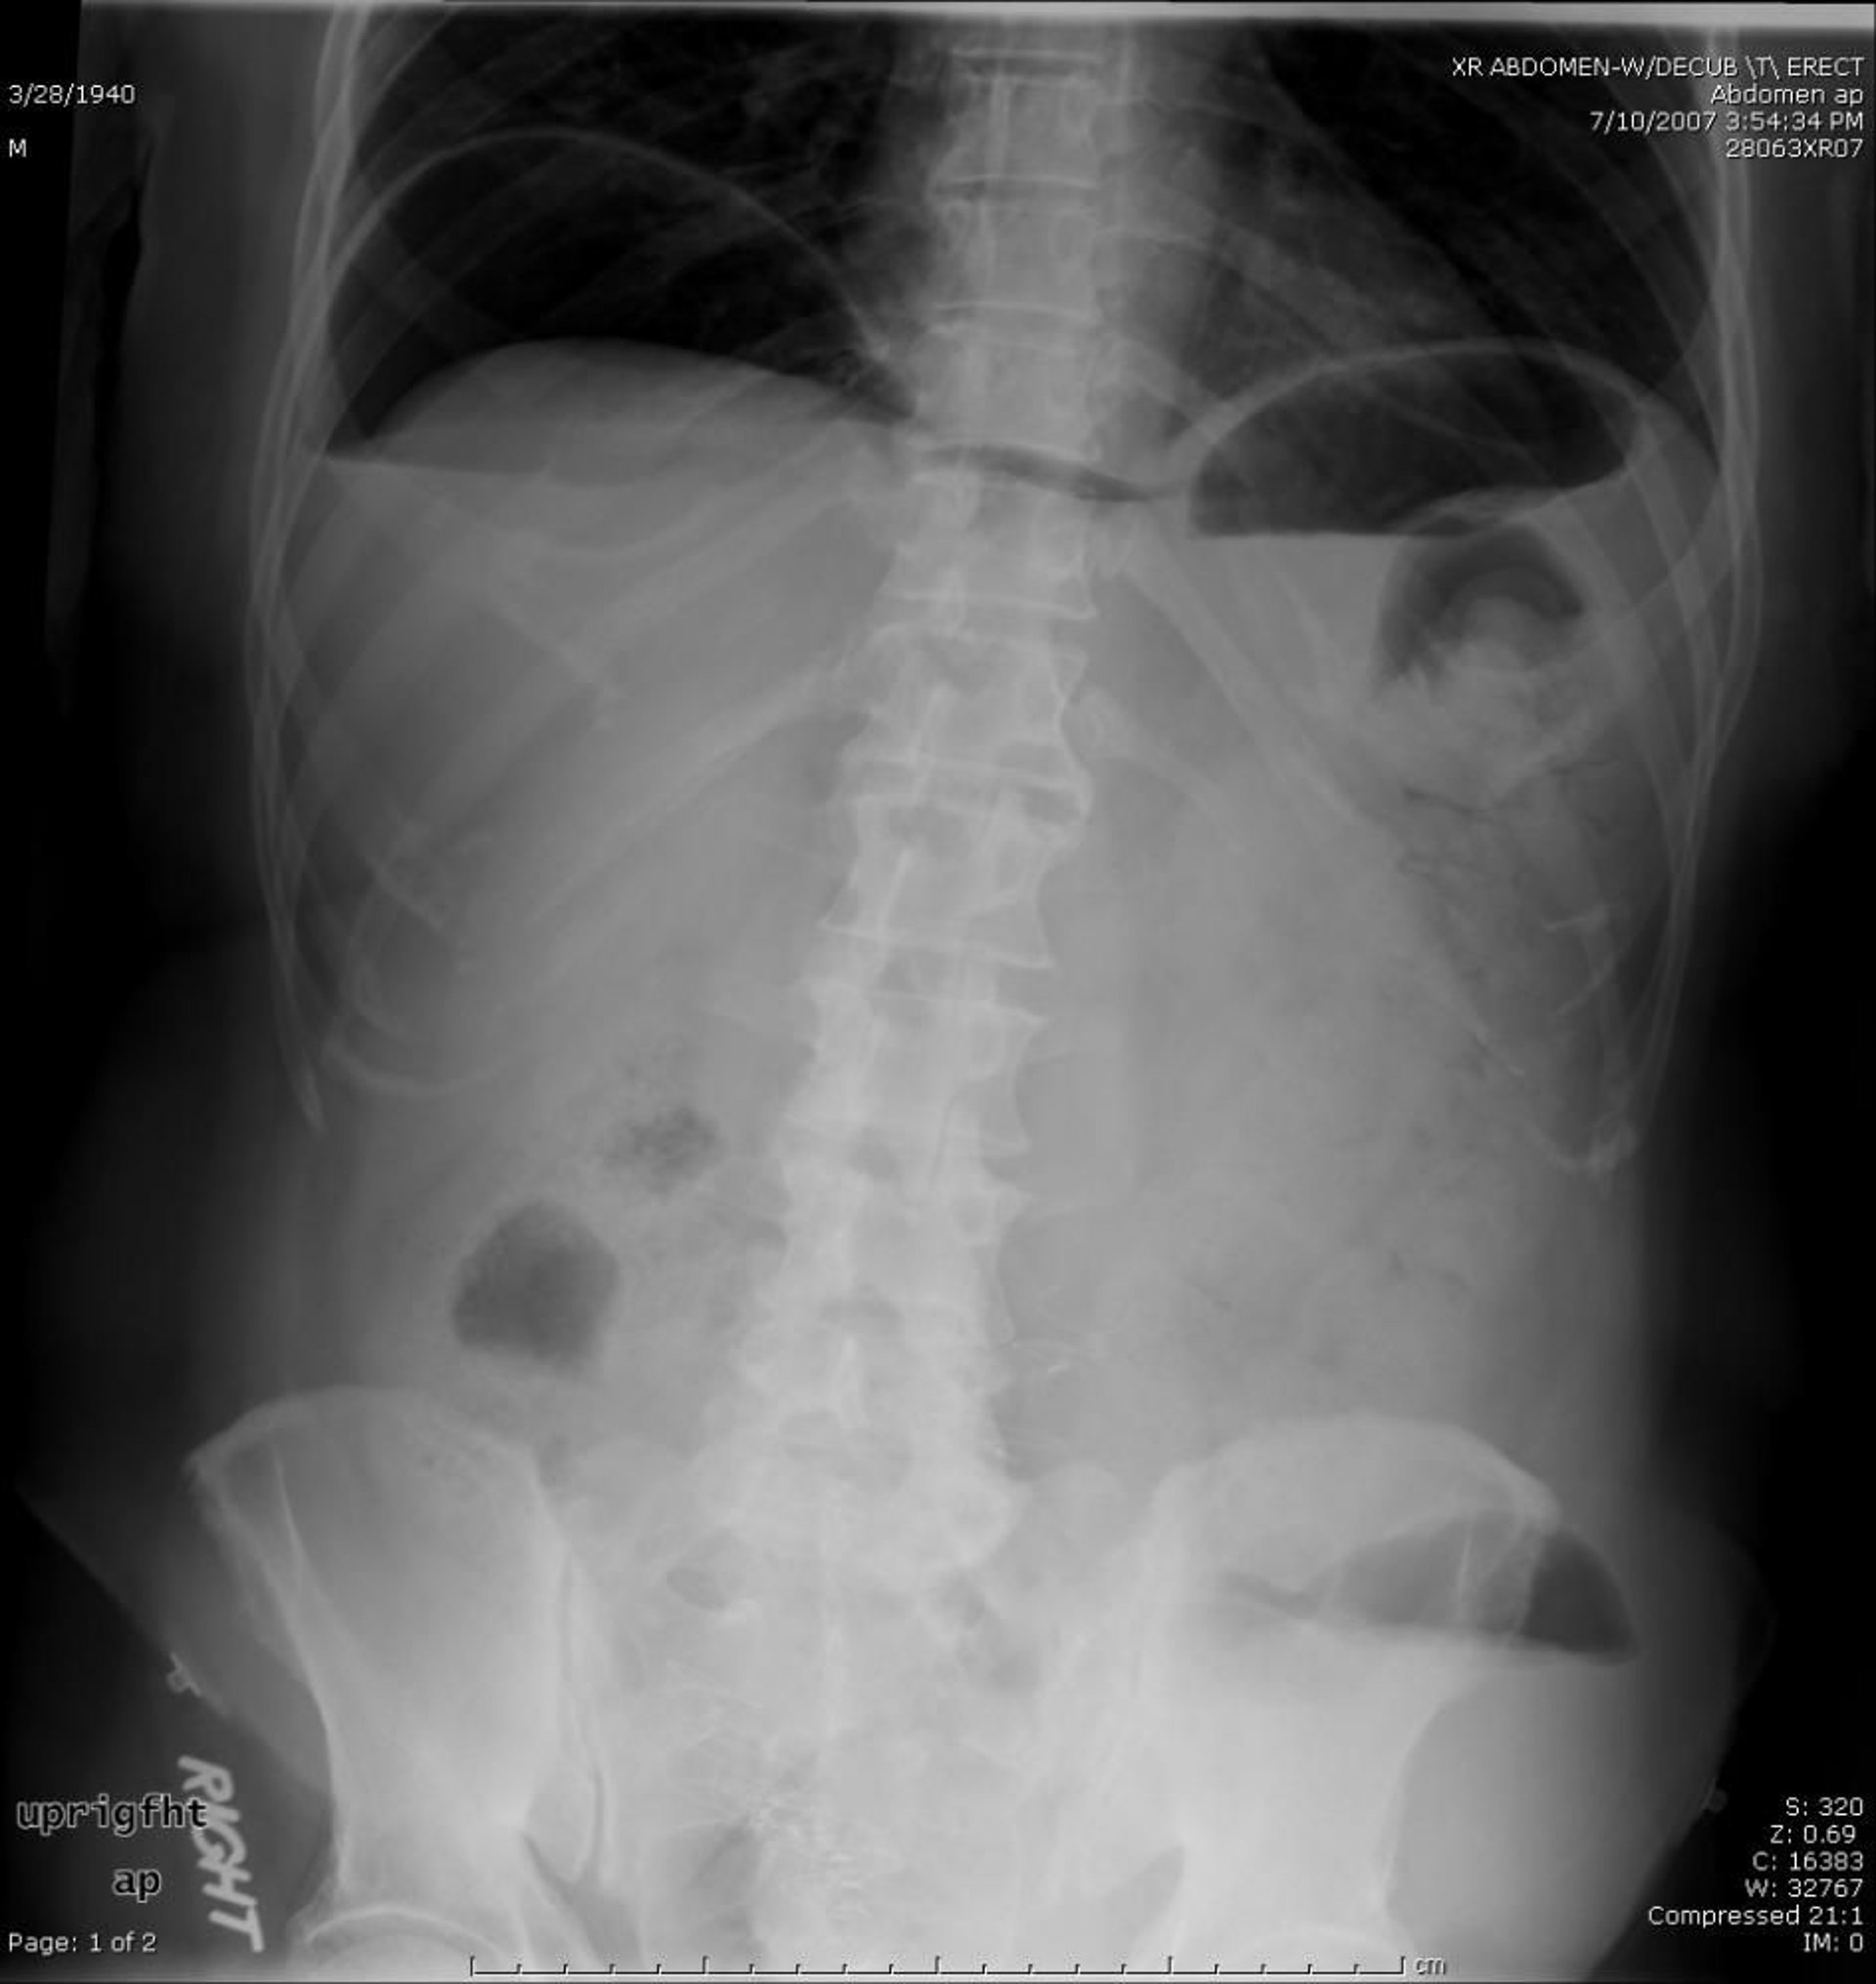

Aria libera

Questa RX addominale mostra l'aria libera causata da una perforazione.

Image provided by Parswa Ansari, MD.